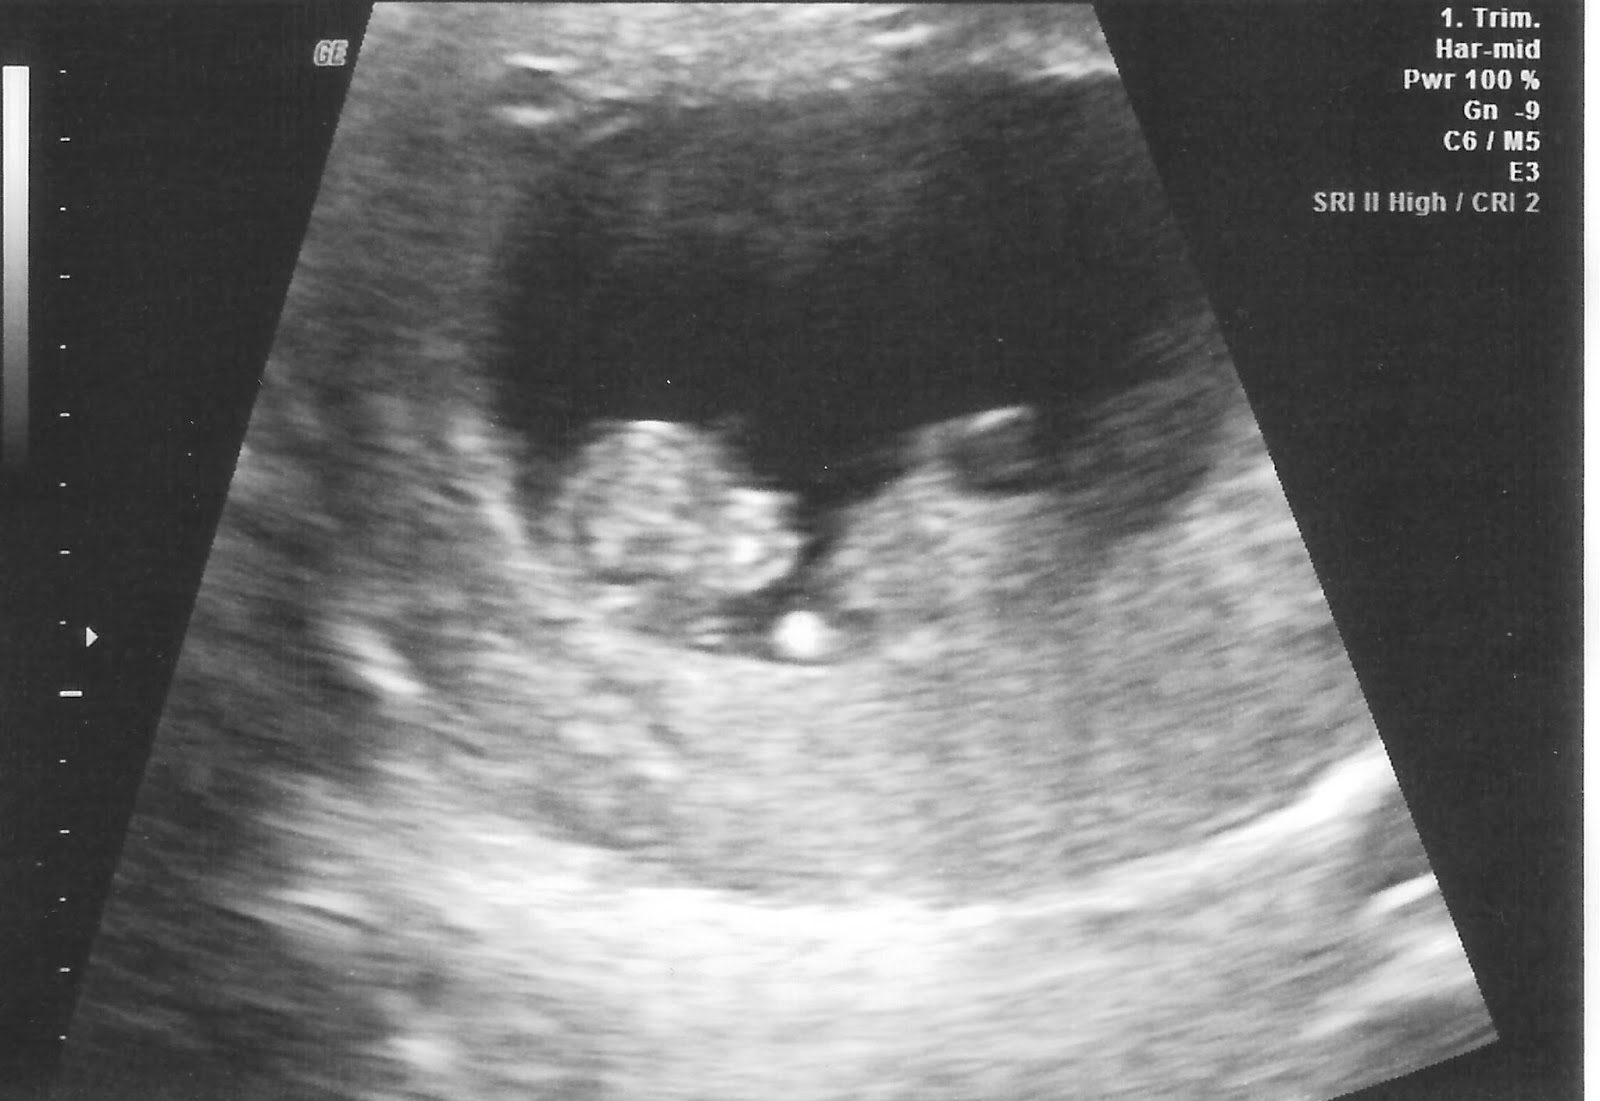

Here's our newest little peanut that should be arriving here in Sept (You have no idea how excited I am that there was only one). This little guy wouldn't stay still at all for any of the measurements the doctor needed. Looks like we're gonna have another wiggle worm on our hands.